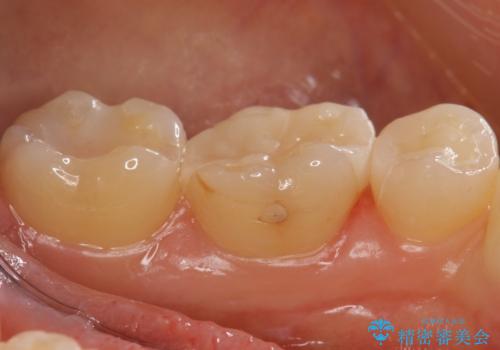

レントゲン画像からは読み取りづらいですが、視診にて歯の一部が黒く透けているのが確認できました。

小さな虫歯でも見落とさずに精度の良い修復をすることで二次う蝕のリスクを減らすことができます。